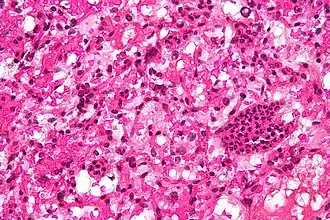

Micrografia de um hemangioblastoma cerebellar.

Hemangioblastomas são tumores do sistema nervoso central originados do sistema vascular, geralmente na meia-idade. Às vezes, esses tumores ocorrem em outros locais, como a medula espinhal e a retina.[1] Podem estar associados a outras doenças, como policitemia (quantidade elevada de células sanguíneas), cistos pancreáticos e síndrome de Von Hippel-Lindau. Os hemangioblastomas são comumente compostos de células estromais em pequenos vasos sanguíneos e geralmente ocorrem no cerebelo, no tronco cerebral ou na medula espinhal. Eles são classificados como tumores de grau um sob o sistema de classificação da Organização Mundial de Saúde.[2]